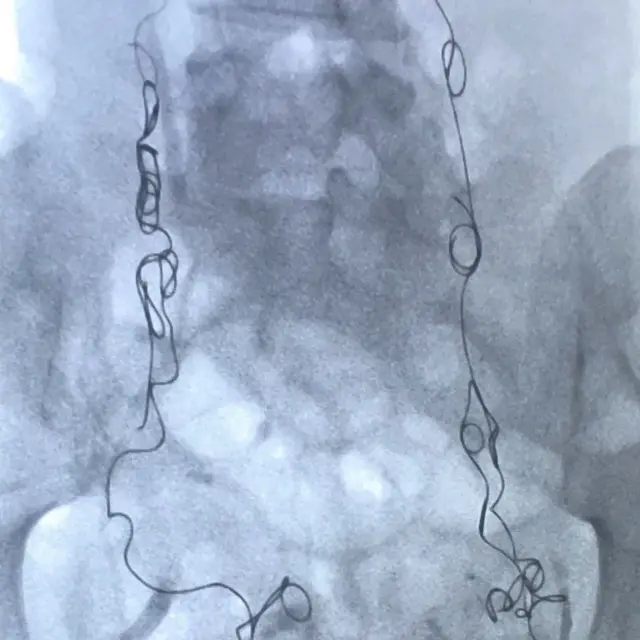

Utorak je, 14. avgust 2018. godine, a ja sam pod anestetikom, ležim na operativnom stolu, dok se metalni kalemi ubacuju u moje vene jajnika i karlice preko katetera u mom vratu.

Nedavno mi je postavljena dijagnoza pelvičnog kongestivnog sindroma (PKS), ili refluksa vene jajnika, kako je još poznat, stanje koje može da izazove nagomilavanje krvi u venama jajnika i karlice, od koje se one šire i počinju da pritiskaju okolne organe.

Emobilizacija koju sam imala 2. avgusta 2018. godine blokirala je moje zakrčene vene metalnim kalemima da ne mogu više da se pune krvlju, uvećavaju i nanose mi bol.